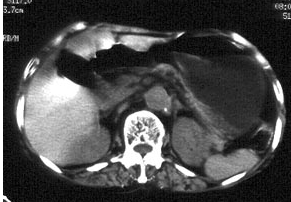

入院查体: 血压18/13kPa,神经系统(—).测血清微量元素均在正常范围,血皮质醇、醛固酮和24h尿VMA均正常.术前CT 诊断:左肾上腺肿瘤,腺瘤可能性大术中见左肾上腺结构正常, 未见占位性病变,紧贴左肾上腺可见一大小约1cm×1.5cm实性物质,呈暗红色,行肿物切除术术后病理:副脾。

诊断:考虑左肾上腺肿瘤,腺瘤可能性大 治疗:术中见左肾上腺结构正常, 未见占位性病变,紧贴左肾上腺可见一大小约1cm×1.5cm实性物质,呈暗红色,行肿物切除术术后病理:副脾。

随访:未完成 讨论:在脾的附近,尤其是在胃脾韧带内和大网膜内,有时会发现一些具有被膜的小结节状脾组织,它们或为单个,或以细条状脾组织与脾相连,这就是副脾。副脾的数量有时可能相当多, 而且可能会在腹腔内呈弥散分布。当副脾与肾上腺位置贴近时,易被误诊为肾上腺肿物,尤其当患者临床有高血压症状时,更会想到腺瘤的可能。但本例患者没有低血钾及周期性麻痹症状,是与腺瘤诊断不相符的,应诊断为原发性高血压。由于这种情况极少见,一般不会想到是副脾。可疑时应行增强扫描,若发现结节与脾脏同时强化,则有助于副脾的判断。另外,若为副脾时同侧肾上腺应为正常形态,而为腺瘤时残余肾上腺常有萎缩改变。